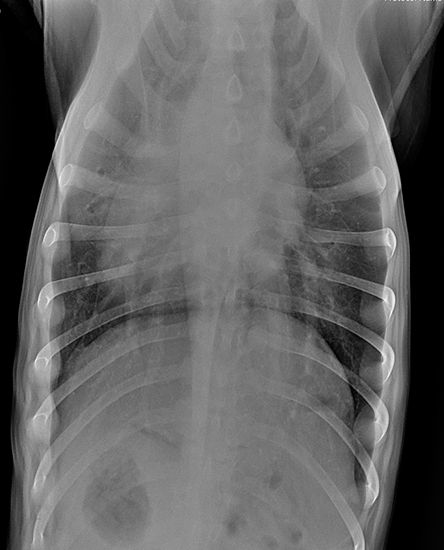

По согласованию с владельцем было принято решение сделать рентген грудной клетки в 2 проекциях и на рентгенограммах были выявлены признаки пневмонии (вероятней всего аспирационной) и бронхита (рисунок 1 и 2). Также был выполнен общий клинический анализ крови по результату которого был выявлен лейкоцитоз.

Рис. 1 и 2

Описание рентгенограмм до начала лечения:

«В вентральной части краниальной и средней долей правого лёгкого выявлены затемнения альвеолярного типа - крайне высока вероятность аспирационной пневмонии. Кроме этого, выявлены затемнения бронхиального типа- возможен бронхит. Затемнения интерстициального неструктурированного типа в остальных долях лёгких должны быть связаны с экспираторной фазой дыхания. Более не выявлено изменений.»